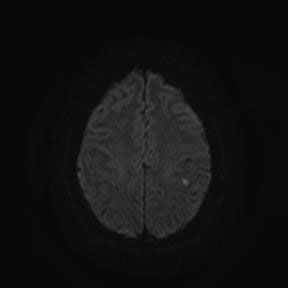

Магнитно-резонансная томография ( МРТ ) - наиболее предпочтительный метод в определении локализации, а главное - в оценке стадии развития ишемического процесса. В острую фазу наибольшую информацию несут диффузионно-взвешенные изображения (сокращенно: ДВИ) - изображения, полученные с помощью специализированной импульсной последовательности, предусмотренной в МР-томографах экспертного класса, которую мы применяем при исследовании всех без исключения пациентов.

При использовании ДВИ можно увидеть минимальное изменение диффузии (скорости движения) жидкости в мозговой ткани на молекулярном уровне, что является первым признаком ишемического повреждения головного мозга. Кроме того, при исследовании головного мозга у пациента с подозрением на лакунарный инфаркт (как и во всех других случаях) мы применяем весь набор импульсных последовательностей, соответствующий международному стандарту, для выявления возможных сопутствующих изменений.

Пациентка 32 года. После посещения невролога обратилась в кабинет МРТ для исключения системного поражения центральной нервной системы с предварительным диагнозом "транзиторная ишемическая атака".

При сканировании головного мозга в нескольких режимах в кортикальных отделах левой теменной доли был обнаружен лакунарный инфаркт диаметром 7мм. Острый инфаркт хорошо виден на ДВИ (импульсная последовательность, доступная в томографах экспертного класса), но плохо виден в режиме с подавлением сигнала от свободной жидкости.

Правильно и вовремя поставленный диагноз, включающий учет причинно-следственных взаимосвязей в развитии патологического процесса, чему значительно способствует описанный выше метод МР-обследования, предопределят тактику лечебных мероприятий.